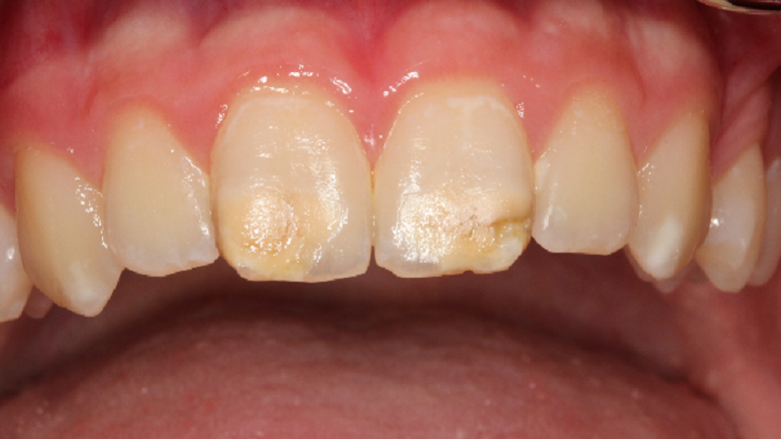

The anterior teeth are often affected as well. The discoloration and abrasion of the surface have an evident aesthetic impact, with consequent psychological effects for the child. (Photograph: Prof. Norbert Krämer)

With MIH, permanent anterior teeth and, increasingly, second primary molars often present with defective structures. Clinically, the severity may vary greatly, from a single cusp to the entire surface of the tooth. The mild form of MIH appears as white-yellowish or yellow-brown irregular opacities of the occlusal surface or cusps. The severe form exhibits chipped or abraded enamel and dentine of varying degrees. The affected patients suffer from pain when drinking, eating and brushing their teeth.